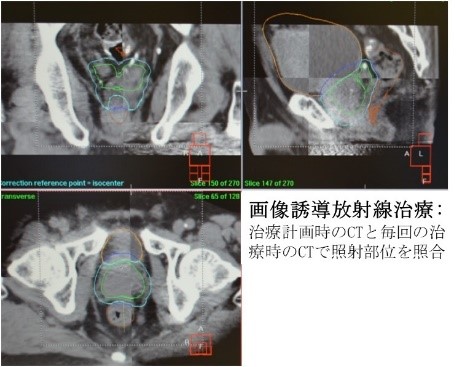

画像誘導放射線治療(IGRT; Image Guided Radiation Therapy)

放射線治療では可能な限り正しい部位に照射することが重要です。高精度放射線治療である定位放射線照射(STI)や強度変調放射線治療(IMRT, VMAT)で狙い撃ちをしても、実際の放射線治療時の照射位置がずれてしまっては、治療効果が保持されないだけでなく副作用も増加してしまいます。当科では、放射線治療装置に付属しているCTを用いて治療前に腫瘍の位置がわかる画像を取得し、照射部位と腫瘍位置のズレがないかどうかを確認した上で照射を開始することで、より正確な放射線治療を実践しています。定位放射線照射(STI)や強度変調放射線治療(IMRT, VMAT)に画像誘導放射線治療(IGRT)を併用することで、高い治療効果で軽い副作用を目指した放射線治療を行っています。